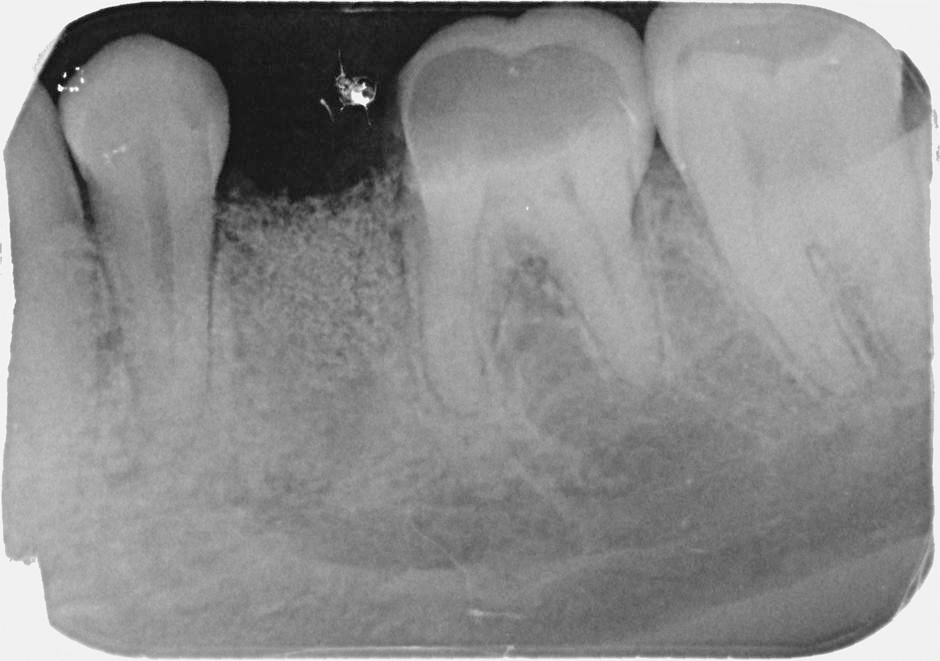

Při ztrátě molárů a premolárů v horní čelisti a jejich náhradě implantáty se často setkáváme s nedostatečnou vertikální nabídkou kosti pod čelistní dutinou, často doprovázenou i nedostatečnou horizontální nabídkou a sníženou kvalitou kosti

(v oblasti 2. premoláru v 50%, v oblasti moláru až v 80% případů nedostatečná kostní nabídka)

Od roku 1985 je tento problém řešen augmentační operací nazývanou sinus lift.

Jedná se o vyzvednutí membrány, která čelistní dutinu vystýlá, pod vyzvednutou membránou vznikne kapsa, kam se umístí augmentační materiál, do kterého se zavedou implantáty.

Vhojení implantátů se při této operaci prodlužuje na 6-12 měsíců.